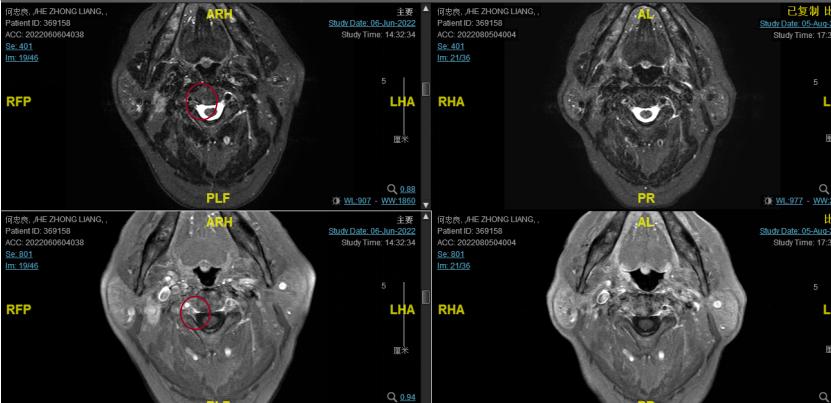

2022-06-29行鼻咽IGRT放疗:GTV1 68Gy/32f 、GTV2 68Gy/32f、CTV1 60Gy/32f、CTV2 50.4Gy/28f。期间同步斯鲁利单抗+尼妥珠单抗+恩度治疗。

2022-08-05(放疗近结束)复查MR, 疗效评价:CR。鼻咽部肿物及咽后转移淋巴结颈部转移淋巴结均达到CR。